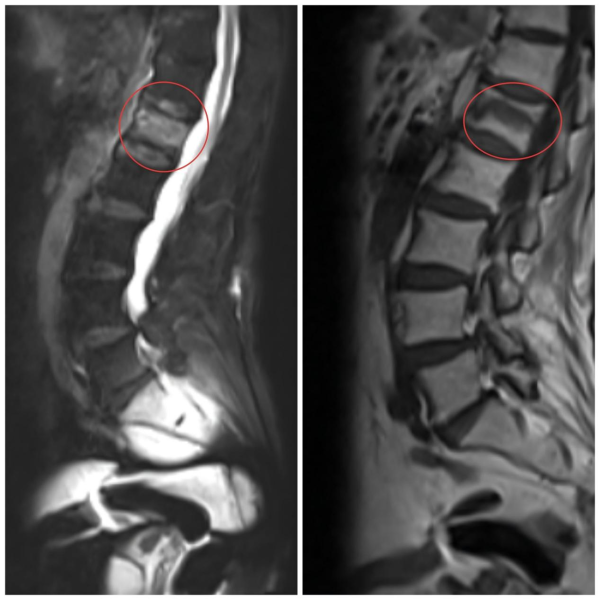

图1:术前腰椎MRI检查明确诊断L1骨折